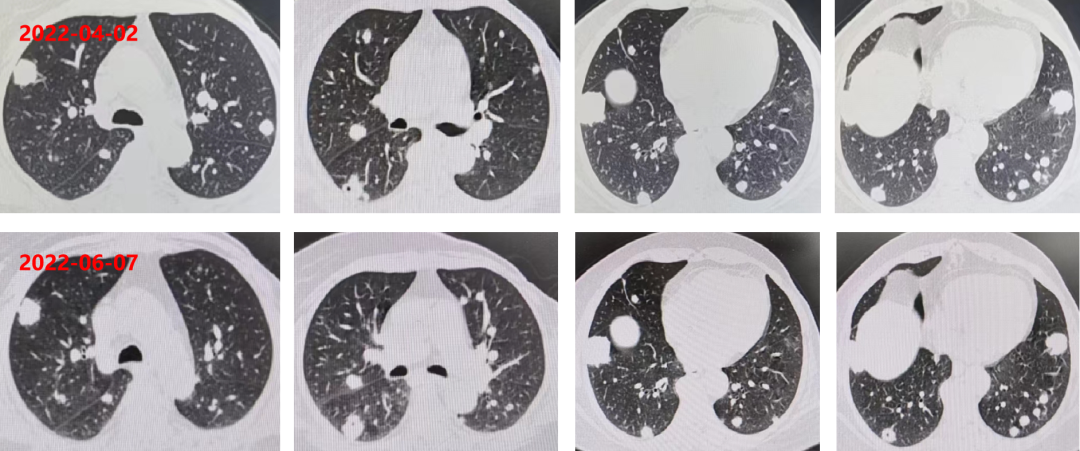

2022-04-02 复查CEA:260.6ng/ml(逐渐升高)。

胸腹部增强CT:双肺多发转移瘤,较前片相比增大(较大者位于右肺下叶,长径约3.4cm,靶病灶增大,出现新病灶),直肠壁和肝左叶病灶未见变化。

疗效评估PD。

2022-06-07 复查 CEA:266.3ng/ml。

胸腹部增强CT:双肺多发转移瘤,较前片相比变化不大(较大者位于右肺下叶,长径约3.3cm,靶病灶与非靶病灶未见明显变化)。

疗效评估SD。